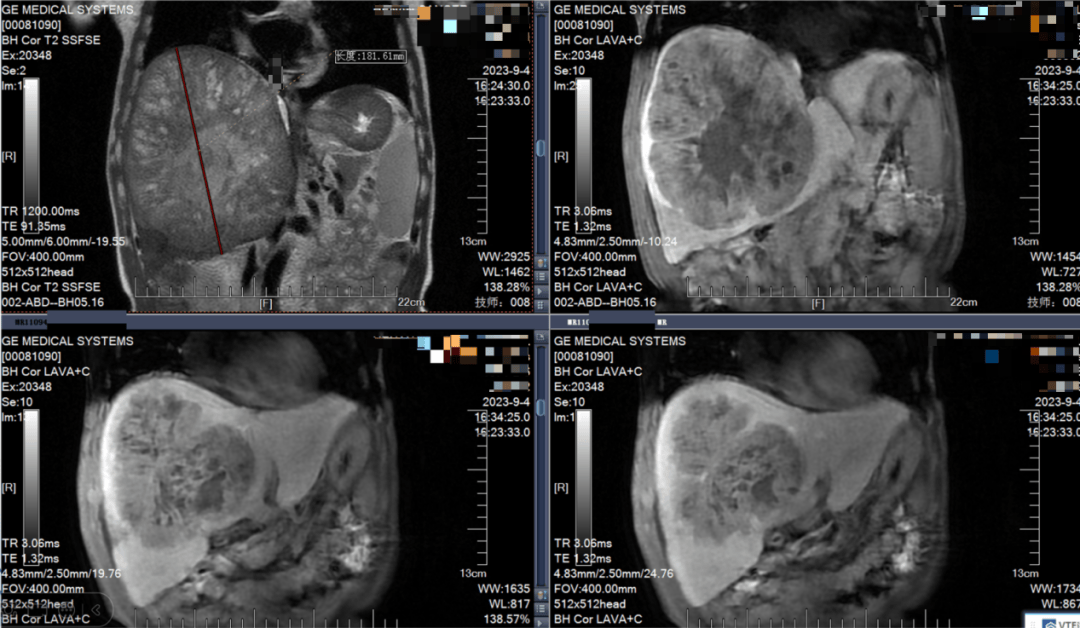

进一步的核磁共振检查结果显示:王先生的肝脏肿瘤巨大,直径长达18.16 cm,几乎占据整个右半肝。不仅如此,肿瘤的位置极为凶险,它紧紧压迫着肝脏血液进出的“生命枢纽”——第一肝门和第二肝门,并侵袭多条邻近的血管。根据诊断,王先生为原发性肝癌IIIa期(CNLC分期),无法直接手术切除,这也意味着治愈的希望变得渺茫。

2023年9月4日 MRI